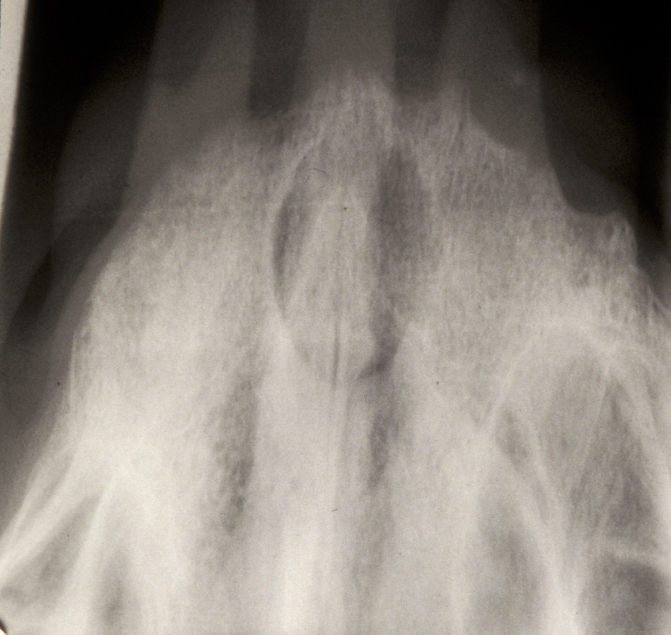

Radicular cyst – in a non-vital tooth, this cyst appears as a rounded periapical radiolucency in an X-ray radiograph, with loss of lamina dura (bone surrounding the tooth socket) and a sclerotic margin if it is a long-standing lesion. Figure 1 shows an example.